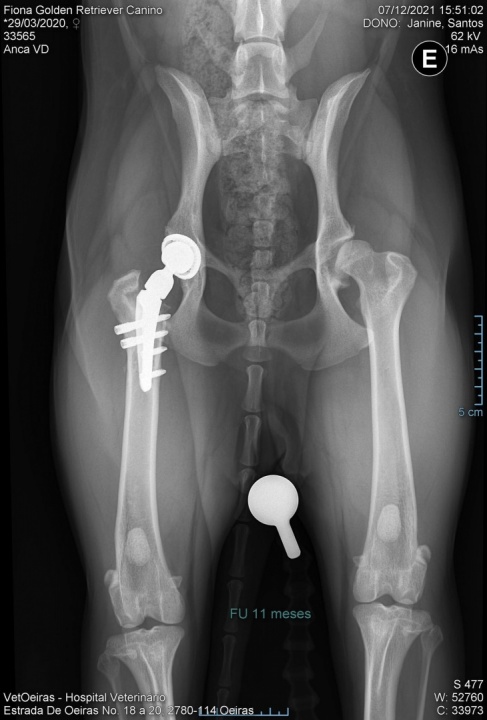

A Fiona tem displasia da anca severa. Já tem uma prótese do lado direito, agora precisa da segunda prótese para uma vida feliz e cheia de brincadeiras.

A Fiona faz parte da nossa família desde as 8 semanas, sempre foi uma cadela muito brincalhona e doce. Infelizmente, aos 9 meses ela deixou de querer brincar, passava o dia deitada com um ar triste e apresentava dificuldades a caminhar. O nosso medo confirmou-se com o diagnóstico de displasia da anca bilateral severa. Foi operada de urgência à anca direita para receber a primeira prótese, o que exigiu um esforço enorme, um custo de mais de 3500€. Ao qual se somou os custos das consultas pós-operatorio e as deslocações até lisboa, ao Vetoeiras.

Agora com 1 ano e 9 meses, chegou o momento de operar a patinha esquerda para receber a segunda prótese de anca, que ainda provoca dores e desconforto. A cirurgia tem um custo de cerca de 3500€, um valor muito alto para conseguirmos suportar novamente, por isso estamos aqui de coração apertadinho a pedir ajuda, cada € poderá fazer a diferença.